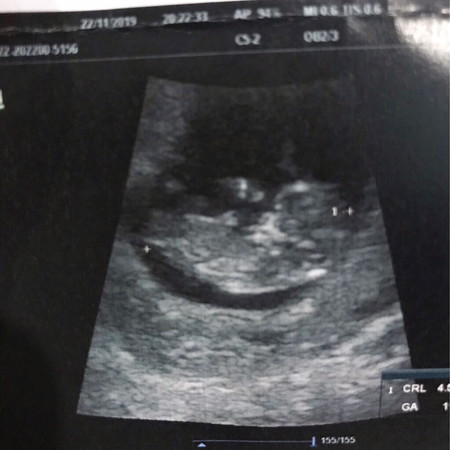

12วีค

ดีใจมากๆที่ได้เห็นลูกน้อยขยับแขน ขยับขา ตื่นเต้นที่สุดหลังจากรอซาวด์มานาน ตอนแรกหมอจะไม่ซาวด์ให้ บอกว่าน้องยังตัวเล็กมาก แต่อิแม่ต้องการเห็นลูกมากๆ เลยขอซาวด์ให้ได้ ความรู้สึกมากมายบอกไม่ถูก ดีใจที่สุดเลยค่ะ ? แม่บ้านไหน 12วีคบ้าง เอารูปหนูมาอวดหน่อยจ้า ?